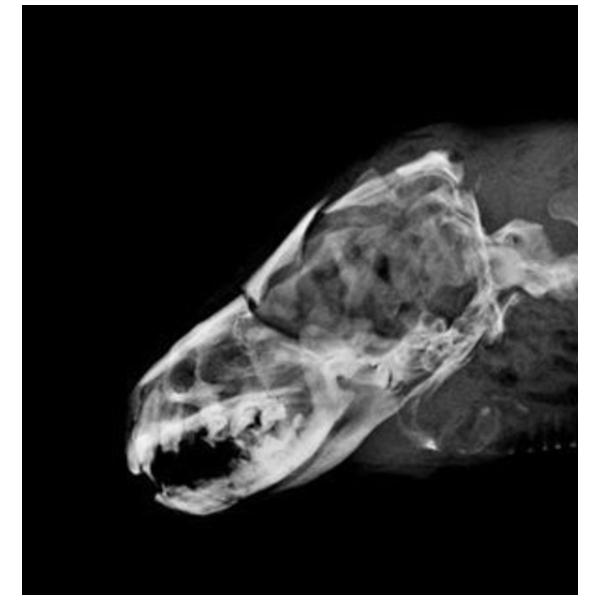

編號D105002水獺。成年雄性可見睪丸,體重5.95Kg,身長106cm、胸徑36.5cm,口鼻流大量鮮血,受理時仍為溫體但已無呼吸心跳。X光檢查頭骨粉碎性骨折、下頷骨骨折、肺前葉出血。死因判定為強烈外力撞擊頭部造成死亡。